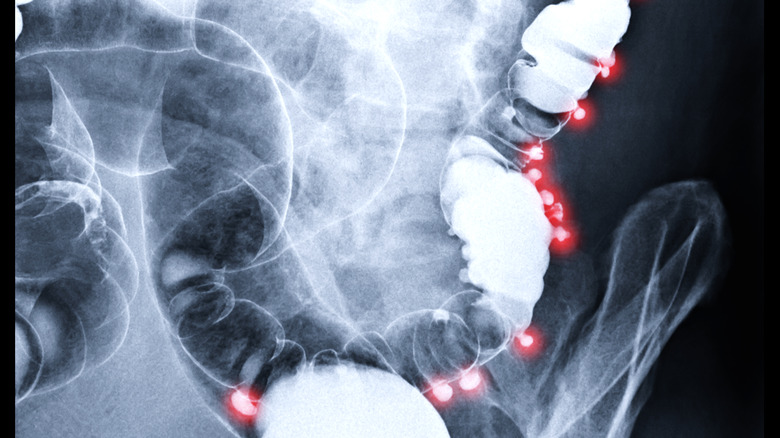

Diverticulitis

We like to think of the intestines, both large and small, as a perfectly shaped tube. And for most of the GI tract, this is true. However, parts of the large intestine can be pocked with small pouches or bulges called diverticula (via the Cleveland Clinic). The presence of diverticula in the colon is common and generally non-problematic. However, if one of these pouches becomes inflamed, abdominal pain can occur. This condition is called diverticulitis. The development of diverticulitis is complicated. A lack of fiber in the diet may be a major contributor, it can cause "a buildup of waste (constipation) in your colon." When you are constipated, the walls of your colon feel the additional pressure, which can lead to the formation of diverticula in your colon's "weak areas."

The characteristic symptoms of the condition may include left lower quadrant pain, fever, nausea and/or vomiting, and (occasional) rectal bleeding. Notably, the diagnosis of diverticulitis consists of multiple modalities, including blood tests, CT scans, colonoscopies and stool sample examinations, to name a few. Treatment consists of various antibiotic options, as well as pain medication and changes to diet. Sometimes, though, diverticulitis is severe enough to warrant the removal of the inflamed section of the colon.